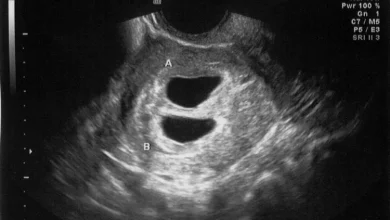

Manfaat dan Prosedur USG Transvaginal Selama Kehamilan

Selama kehamilan, pemantauan kesehatan janin menjadi prioritas utama bagi ibu hamil dan penyedia layanan kesehatan mereka. Salah satu alat yang…